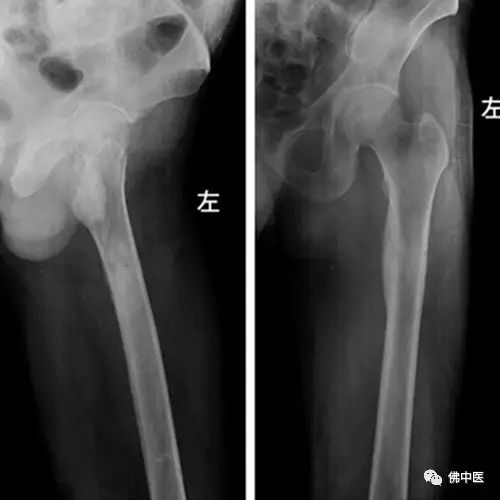

术后X光片